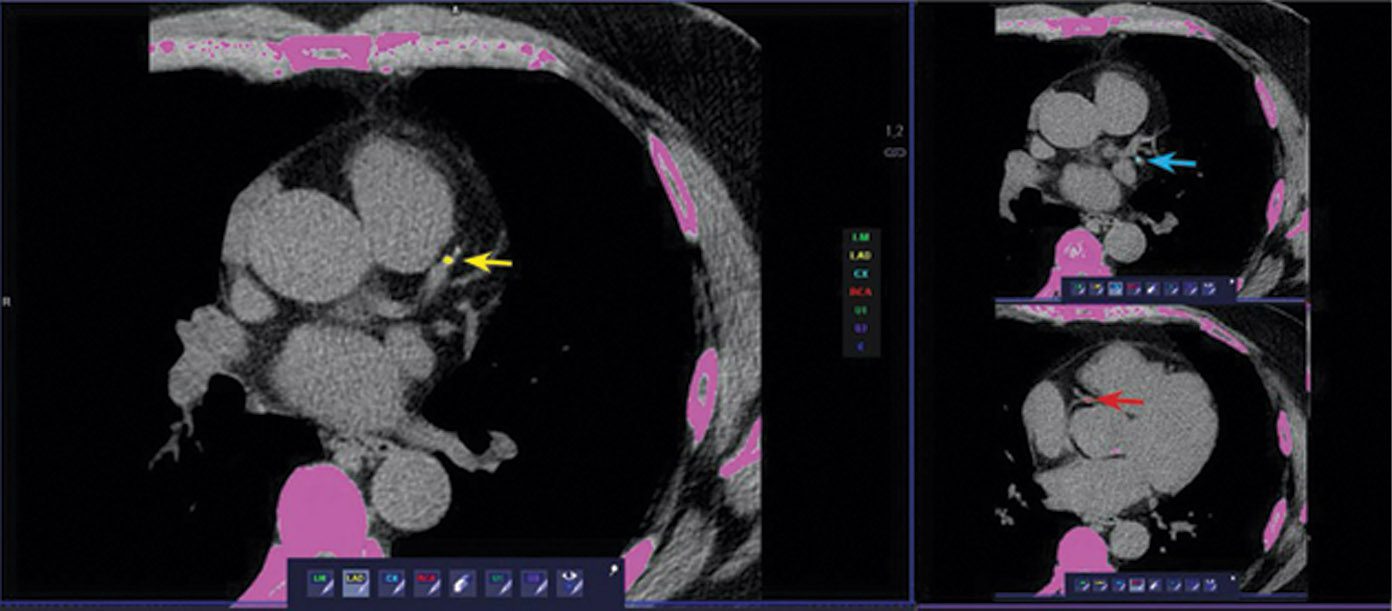

Cureus Coronary Artery Calcium Score A Reliable Indicator of Calcium Score Test Lad  Results from the scan may be used. Web  the coronary artery calcium (cac) scan is an important tool in cardiovascular risk stratification and determination of appropriate. Web  coronary calcium scan results can help determine the risk of heart attacks or strokes. Web  in asymptomatic patients without established atherosclerotic cardiovascular disease (ascvd), the presence of coronary. Web  the coronary artery calcium. Calcium Score Test Lad.